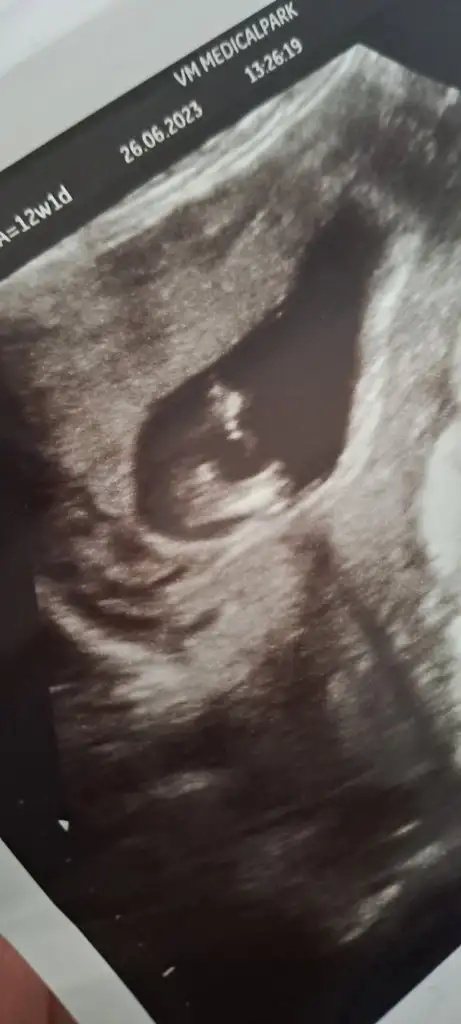

Z Zzzzz00 canım bana da tahminde bulunur musun lutfen 12+1 haftalik teşekkür ederim

• 20230626_155209.webp

20,3 KB · Görüntüleme: 43

• 20230626_155202.webp

17,9 KB · Görüntüleme: 44